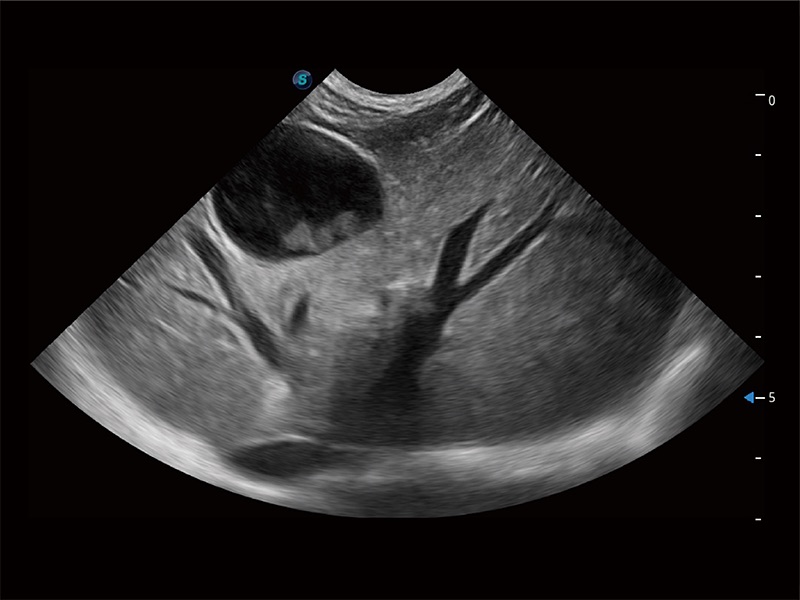

为精细结构及组织边缘提供高清晰度的图像和更大的成像视野。帮助减轻医生的用眼疲劳,快速精准获得测量的数据。

ProPet 80 全新的动物超声智能软件和丰富的探头群,为动物医生提供了高清晰度和精细分辨率的图像,无论在宠物、马科、畜牧还是实验室动物等应用中都可以轻松应对,为您的日常工作带来满意的体验。